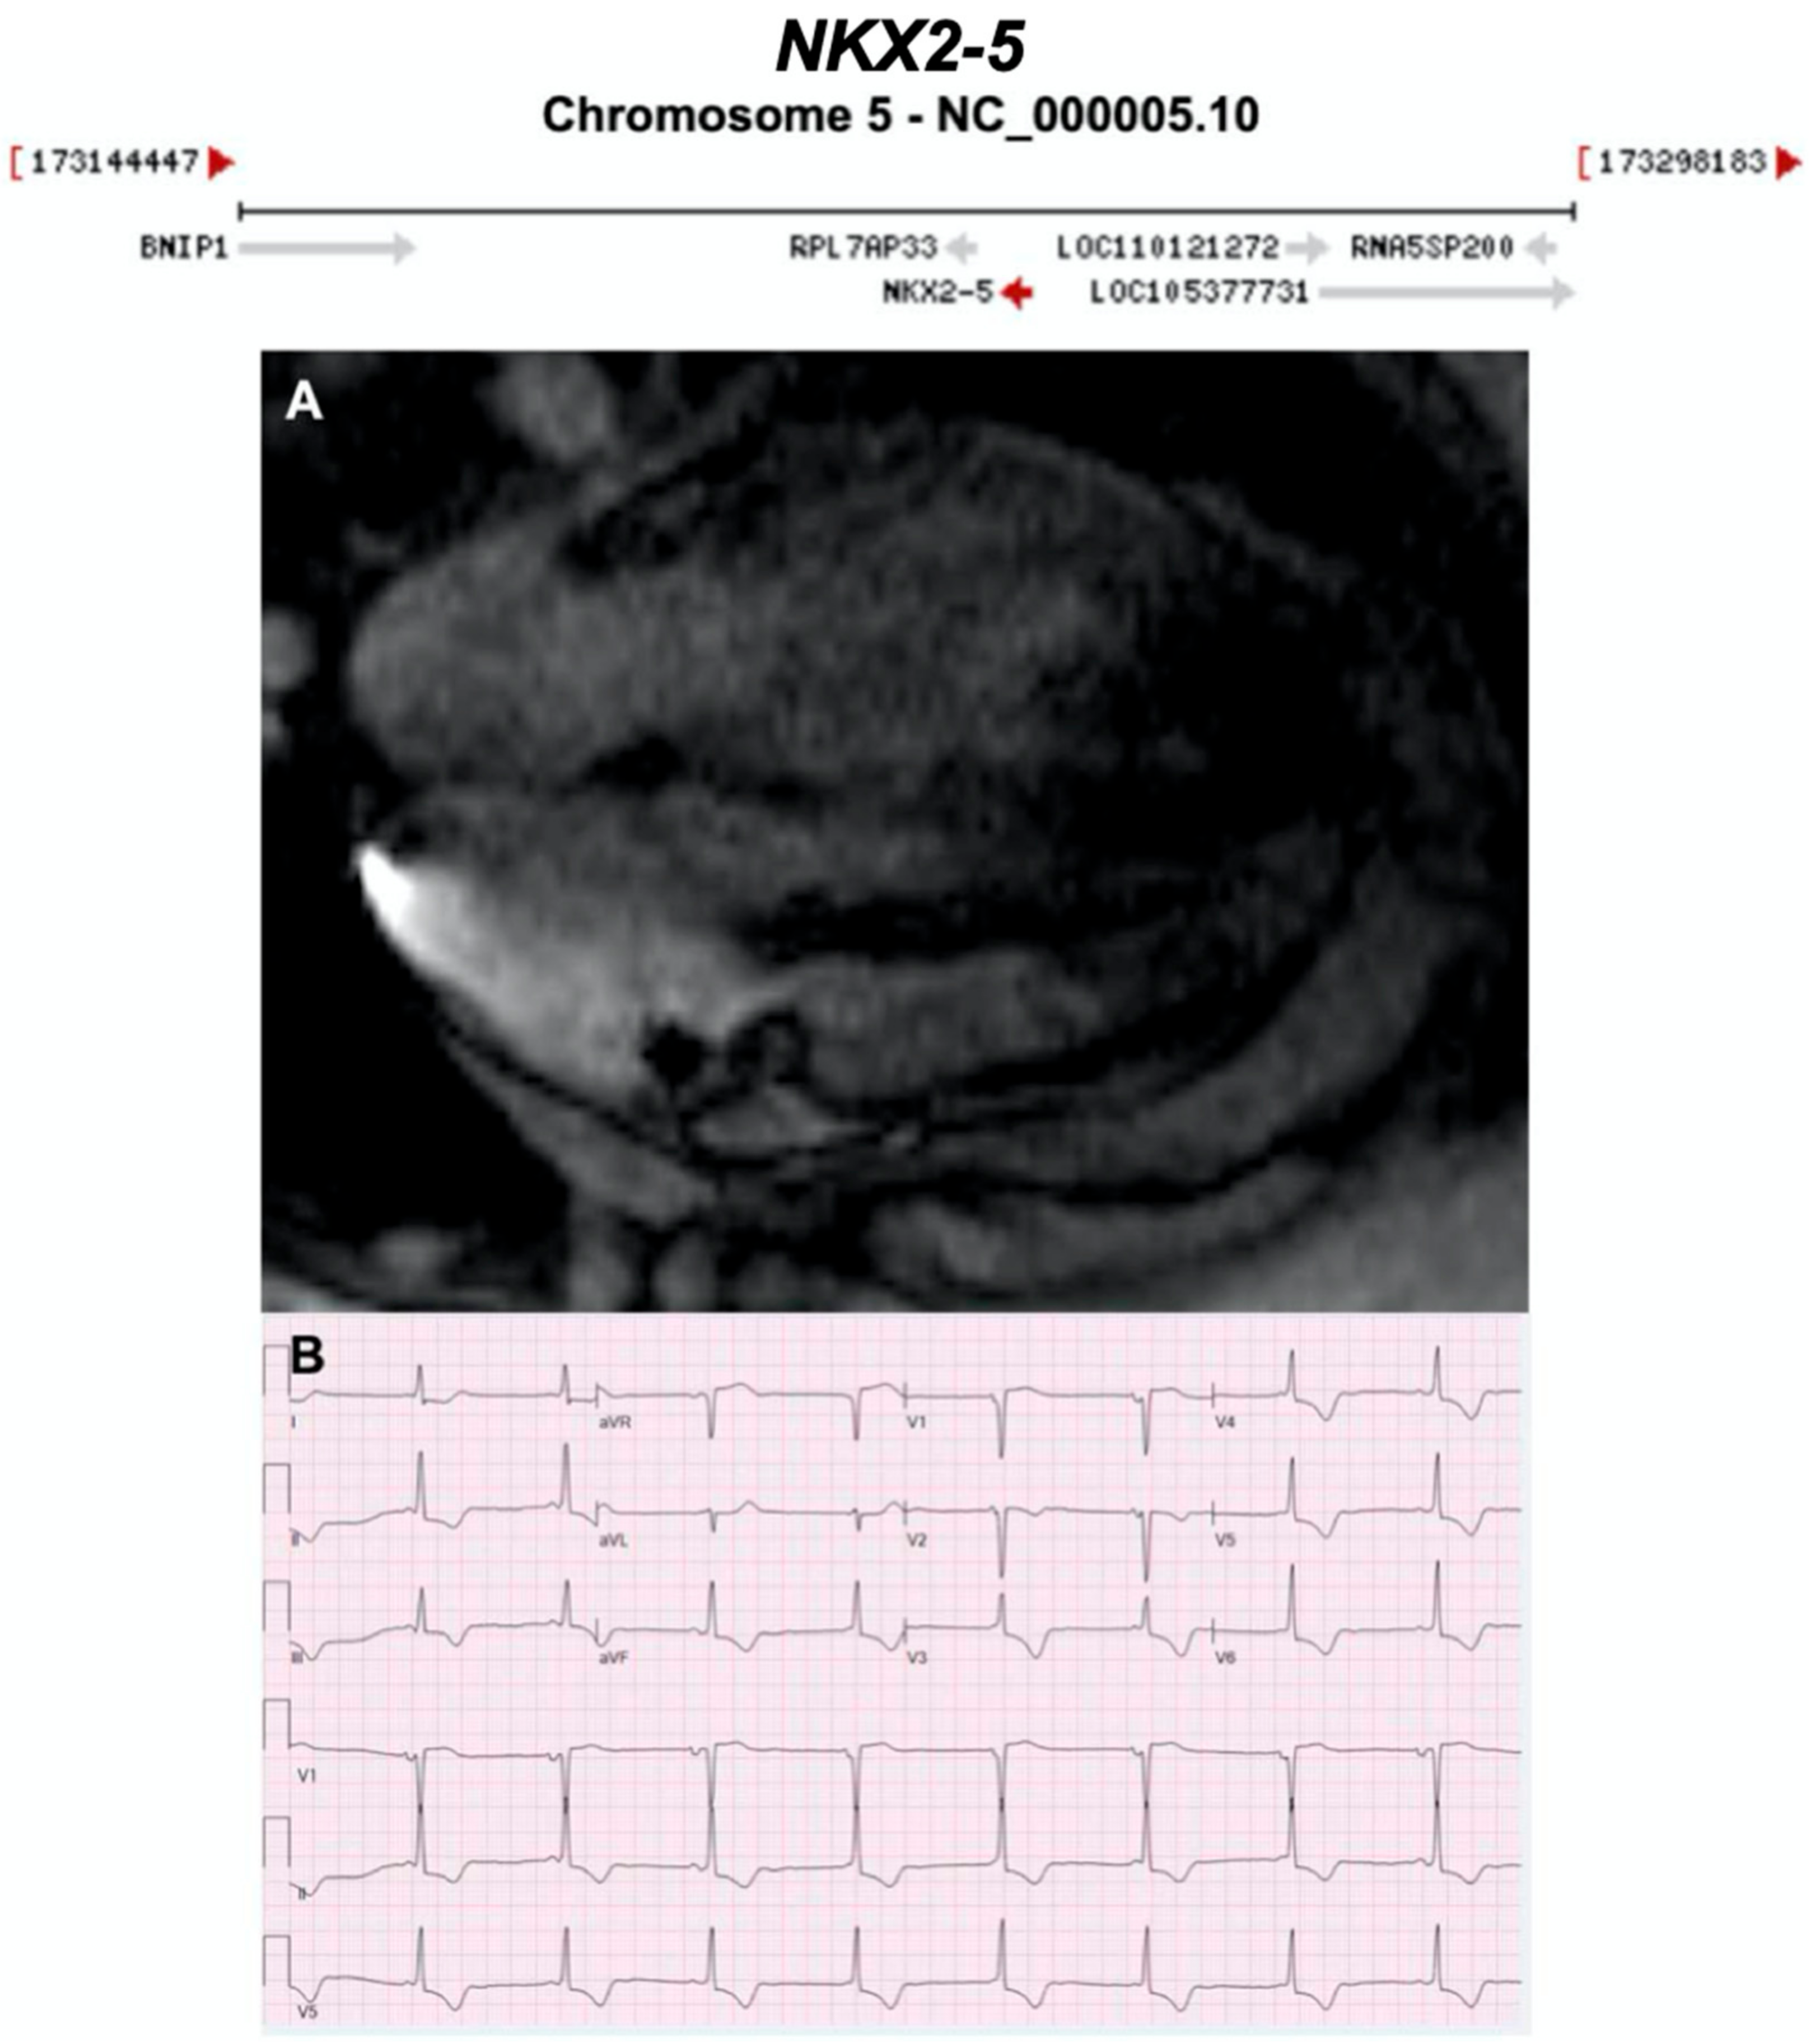

Figure 19.

Exemplar MRI and ECG finding found in ACM patients with NKX2-5 mutations. (A) A cardiac MRI of a patient with NKX2-5 c.471_472delCA variant showing non-dilated hypokinetic ventricle, no valvular heart disease, no LGE; (B) ECG finding of a different patient with the same NKX2-5 mutation as in (A). CMR = cardiovascular magnetic resonance; ECG = electrocardiogram; LGE = late gadolinium enhancement; LV = left Ventricle; RV = right Ventricle. Gene location images taken from https://www.ncbi.nlm.nih.gov/gene/.

3.2.15. NK2 Homeobox 5 (NKX2-5) (Encoded by NKX2-5)

NKX2-5 encodes a homeodomain-containing transcription factor essential for cardiac morphogenesis. Pathogenic variants in NKX2-5 cause diverse cardiac phenotypes with variable expressivity [124], most commonly progressive atrioventricular block and congenital heart defects (especially secundum atrial septal defect (ASD)) [125]. NKX2-5 variants have also been implicated in adult-onset DCM [126] and ventricular arrhythmias [127]. The p.Phe145Leu variant in NKX2-5, carried by 1 in 7100 Icelanders, was reported to cause severe adult-onset familial DCM with very high penetrance and an increased risk of SCD [128].